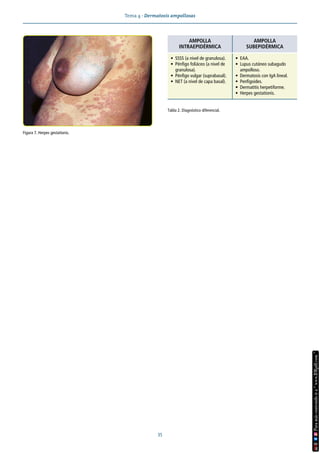

Concepto

La clínica es consecuencia del despegamiento entre los distin-

tos estratos celulares que forman la epidermis o de las distin-

tas láminas que forman la unión dermoepidérmica (UDE). Este

despegamiento se produce por formación de autoanticuerpos

dirigidos contra distintos antígenos implicados en la adhesión

celular en los casos adquiridos y por déficits congénitos de de-